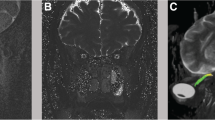

Mean and SD values of total cerebral blood flow (TCBF), total internal jugular flow (TIJF), flows through dominant internal jugular veins (DIJF), nondominant internal jugular veins (NIJF), and total internal jugular flow (TIJF) normalized to total cerebral blood flow are summarized in Table 1. Venous drainage through the primary venous channels is significantly reduced in IIH patient compared with healthy subjects. This difference is further enhanced after normalization with total cerebral blood flow as demonstrated by the smaller p value (p value < 0.004). Example of a 3D MRV rendering of the extra-cranial venous vasculature from a control subject and from an IIH patient demonstrating the increased drainage through secondary channels in IIH is shown in Fig. 2. Means and SDs of morphological measures, CSF production rates and contribution to spinal canal compliance are summarized in Table 2. A trend toward slightly larger ventricular volumes in the IIH was observed. However, this trend was not statistically significant. No difference was found in CSF production rates between IIH and healthy. However, a larger but not significantly different variability in the CSF production was observed. In contrast to the morphological measures, spinal canal compliance contribution is significantly different in IIH and controls. A significantly smaller contribution to spinal canal compliance (0.6 vs. 0.75) was found in IIH (p = 0.026).

Example of Magnetic resonance venography of cervical venous drainage in a control subject (left) and an idiopathic intracranial hypertension (IIH) patient (right). In the healthy subjects, the venous drainage occurs mainly through the jugular veins (arrows) while in the IIH patients an increased drainage through the secondary venous channels (e.g., vertebral, deep cervical, epidural veins; arrowheads) is observed

This finding suggests, for the first time, that the spinal canal plays an important role in the pathophysiology of IIH. It has been documented that ICP fluctuates considerably over a short period of time in IIH. As the spinal canal provides most of the buffering for increased CSF volume, reduced spinal canal compliance buffering provides a good explanation of the impaired regulation of CSF pressure in IIH. This finding further explains why obesity carries an increased risk of IIH. Hogan et al. reported significantly smaller CSF space cross-sectional areas in obese compared with slim subjects. They attributed the smaller CSF area to inward displacement of the neural foraminal contents caused by high abdominal pressure [9]. Therefore, the already compressed spinal canal CSF space in obese subjects is very likely increasing resistance for expansion, thereby reducing the spinal canal compliance buffering. The second important observation of reduced cerebral venous drainage through the primary venous channels is in agreement with an earlier report of increased drainage through secondary venous channels in IIH [2]. As previously suggested, this may reflect increased resistance to venous drainage in IIH.